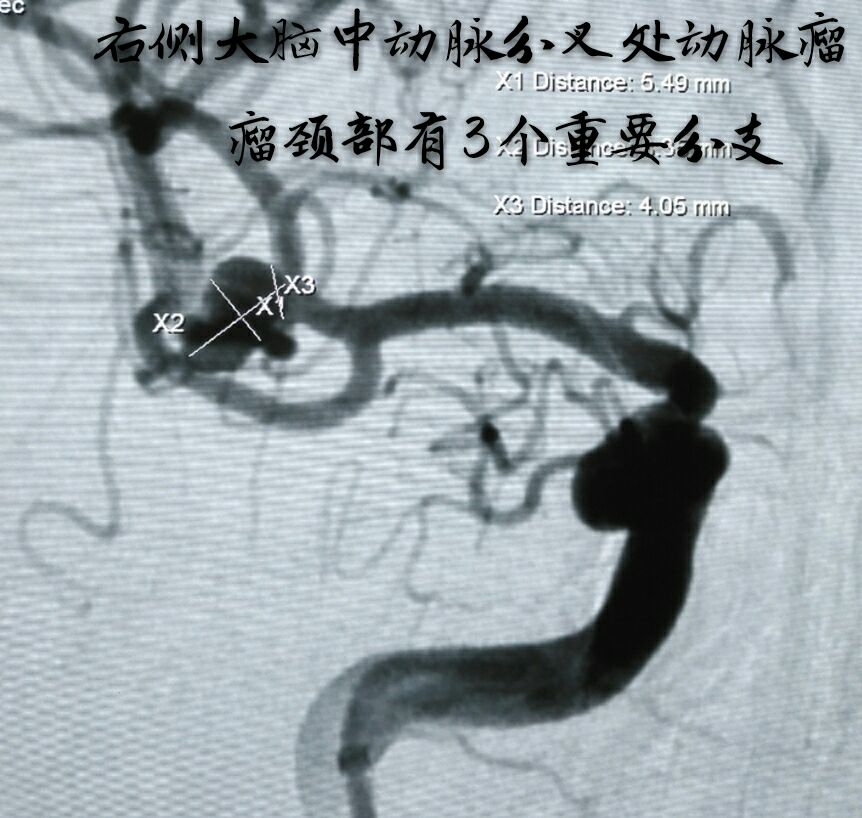

病例十二:中年男性患者,右侧大脑中动脉分叉部动脉瘤,宽颈,形态不规则,瘤颈部分支众多

因瘤颈下方分支与动脉瘤关系密切,角度刁钻,而血管纤细,无法用辅助支架保护,术前做了详细、精准的计划,决定用双微导管技术栓塞